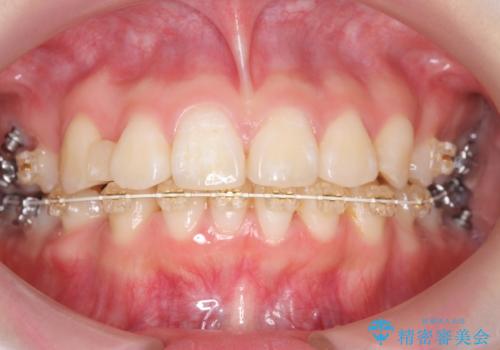

成人式に間に合う 前歯の矯正

- 前歯のがたがたを主訴に来院。

口元も下げたいとのことでした。

成人式の1年前から矯正をはじめ、成人式前に上の前歯の装置を一時的にとりました。

一時的に装置を取ることで、多少治療期間が伸びましたが、それでも、2年かからずに外すことができました。

成人式の時に前歯が下がって、揃った状態で写真を撮ることができ、大変喜んでおられました。